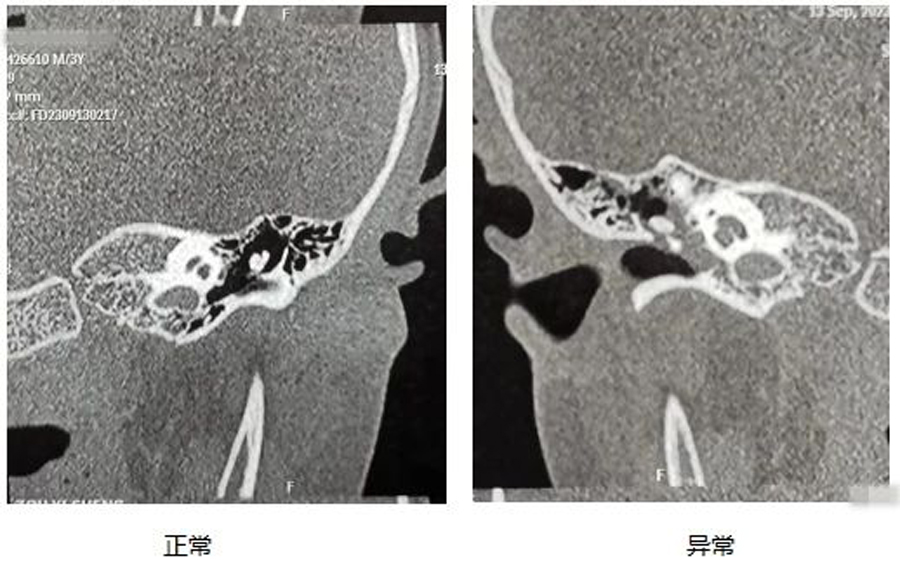

诊断分泌性中耳炎需要做哪些检查?

4.必要时做乳突CT